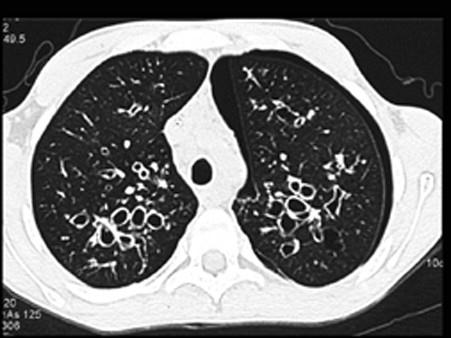

问题 慢性支气管炎的X线表现为 ( )

选项 A、肺纹理增粗 B、肺透亮度增加 C、肺内有液平 D、肺大疱征象 E、肺部有块影

答案 A